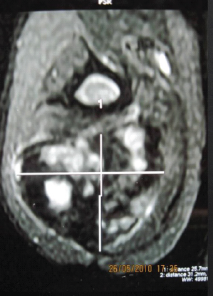

Chronic Thigh Pain in an Adolescent: A Case Report and Literature Review of Desmoplastic Fibroma, A Rare Benign Tumor

Janki Sharan Bhadani , Aayush Choudhary , Alok Kumar , Vaibhav Sanchay , Indrajeet Kumar , Santosh Kumar

………………………………p.206-210